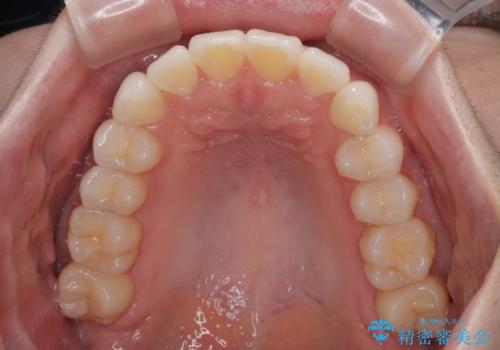

- 上下前歯の叢生を気にして来院された患者様です。

軽度な叢生であり、安価で短期間の治療を規模されていたため、インビザライン・モデレートを用いて矯正治療を行うこととしました。

インビザライン・モデレートは、製作できるアライナーの枚数に制限があるため、移動可能な量に限りがあるものの、インビザライン・ライトよりも枚数が多いため、幅広い症例に対応可能です。